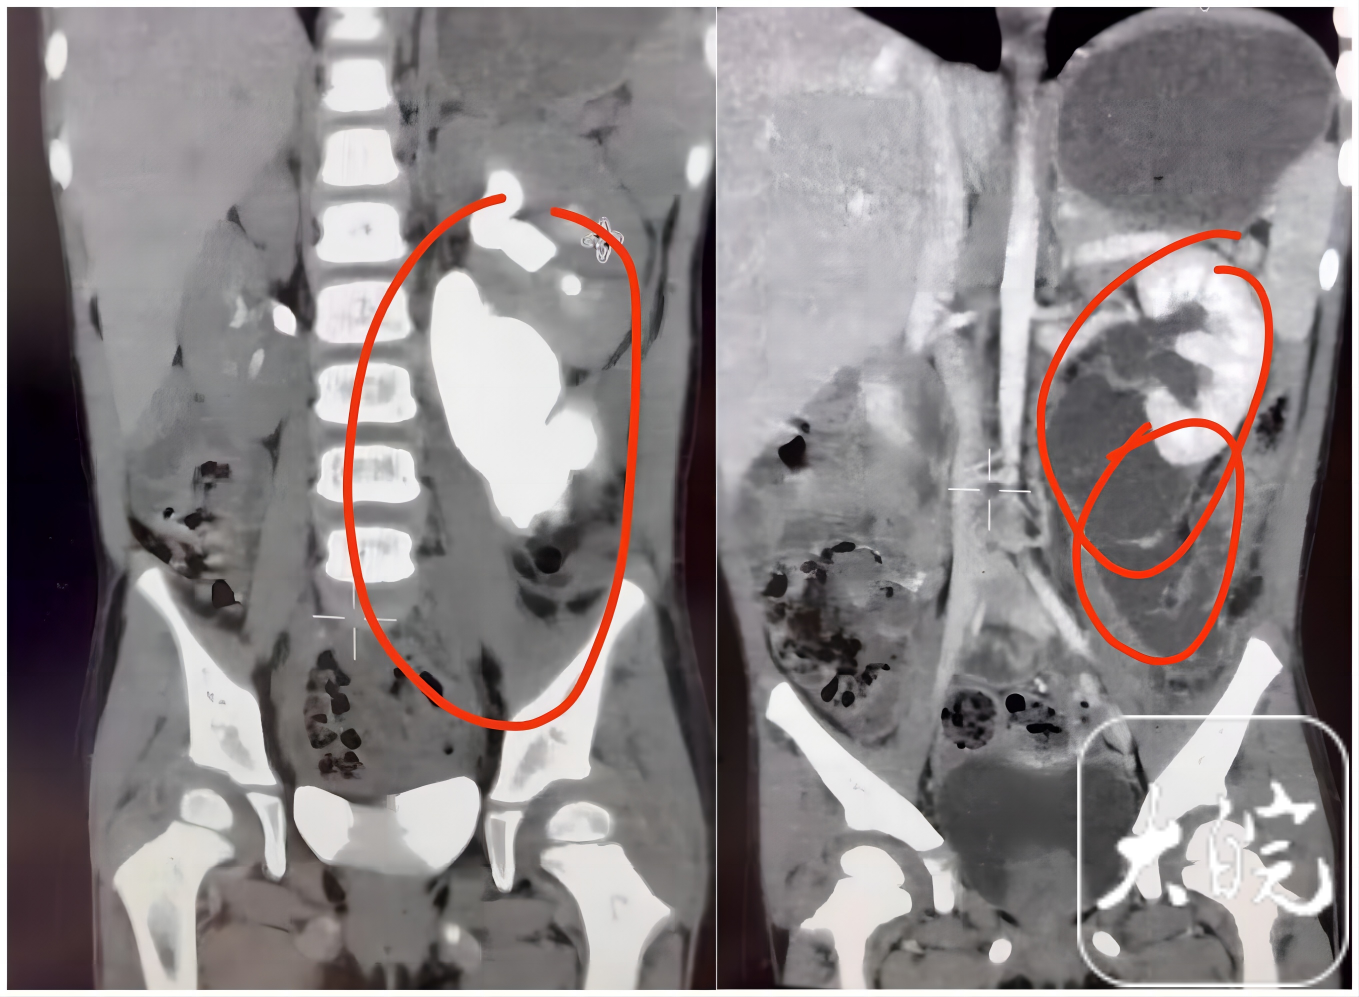

红色圈出来的部分为大量外渗的尿液

“这种泌尿系统损伤十分隐蔽,早期症状往往不明显,极易被忽视。通常是跌倒引发的剧烈震荡,导致肾盂输尿管连接部被撕开断裂,尿液渗漏至腹腔,引发腹部膨胀、疼痛等症状。”曹永胜介绍,因撕裂后肾盂会回缩到肾脏里面、难以牵出吻合,同时输尿管撕裂段不整齐、坏死、回缩,导致输尿管断端和肾盂的距离大而难以吻合修复,另外,大量尿液漏出使组织水肿类似鱼冻状,输尿管断端寻找困难。故修复手术难度极大。